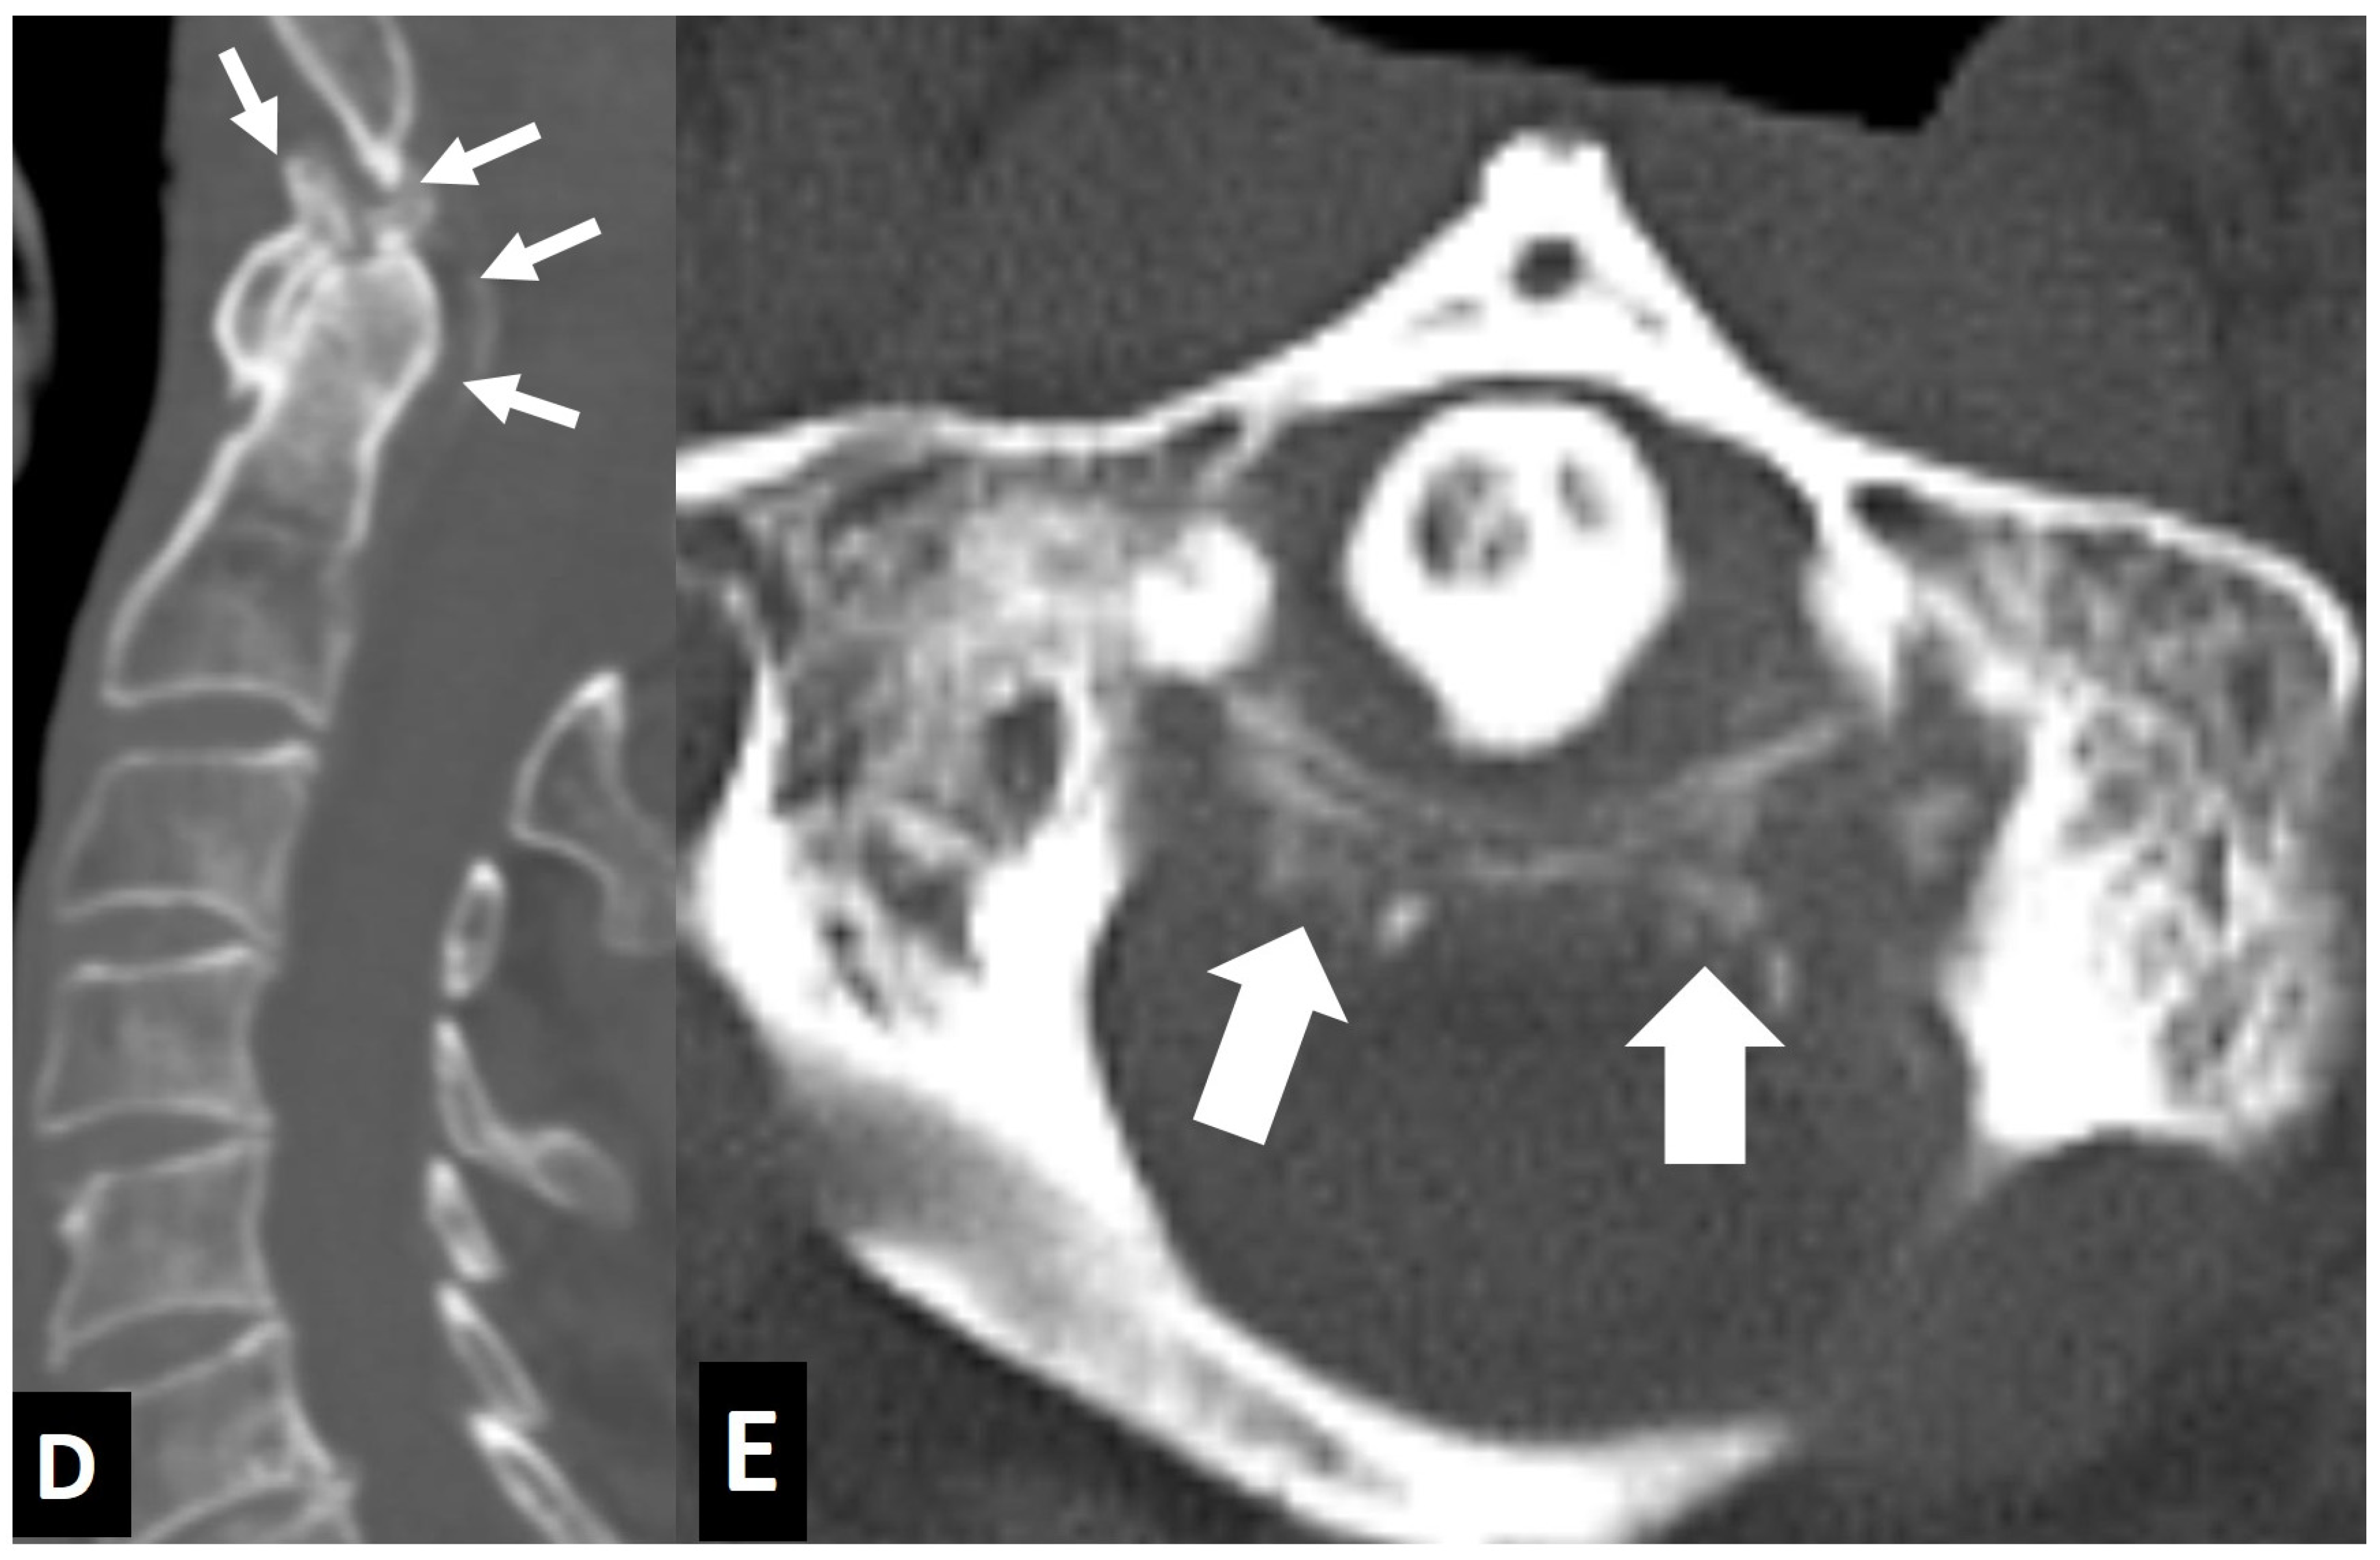

2.1.5. Crystal Deposition

- Ring, D.; Vaccaro, A.R.; Scuderi, G.; Pathria, M.N.; Garfin, S.R. Acute calcific retropharyngeal tendinitis. Clinical presentation and pathological characterization. J. Bone Jt. Surg. Am. 1994, 76, 1636–1642. [Google Scholar] [CrossRef] [PubMed]

- Offiah, C.E.; Hall, E. Acute calcific tendinitis of the longus colli muscle: Spectrum of CT appearances and anatomical correlation. Br. J. Radiol. 2009, 82, e117–e121. [Google Scholar] [CrossRef] [PubMed]

- Bouvet, J.P.; le Parc, J.M.; Michalski, B.; Benlahrache, C.; Auquier, L. Acute neck pain due to calcifications surrounding the odontoid process: The crowned dens syndrome. Arthritis Rheum. 1985, 28, 1417–1420. [Google Scholar] [CrossRef]